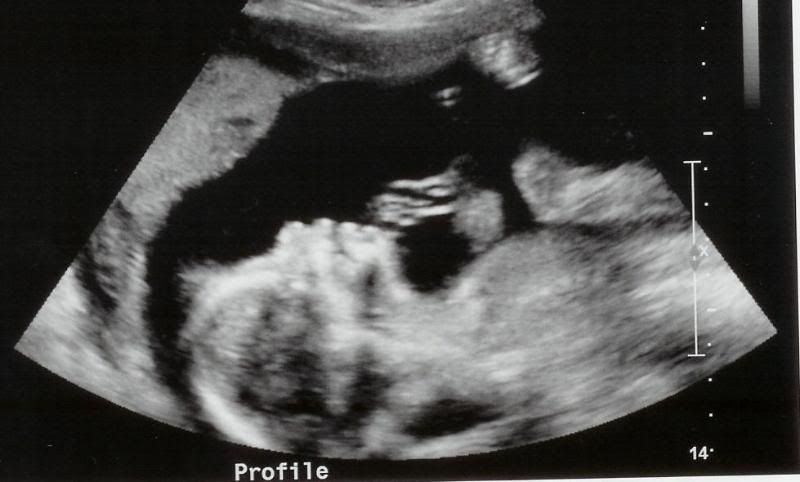

The Ultrasound this morning went wonderfully. The gender of the baby was written down on a card and sealed up without me looking! Also included is a picture of the baby. The U/S technician was so wonderful to me when I told him you were deployed that he printed out 5 pictures for me. You remember with Autumn, they would only give you one. The baby's heart rate measured anywhere from 139 to 144 beats per minute. I saw the head, spine, eye sockets, nose, lips, hands, kidneys, stomach, legs, feet, arms and the most astonishing was the heart. All four chambers beating beautifully. The technician seemed to spend a lot of time around the brain area and I don't know if that means anything or not because they spent a lot of time looking around Autumn's heart last time and this time, not so much. I will get to review the results of my U/S with my doctor in two weeks. Here are the pictures:

Profile

Profile again. Someone (Angie I think) made mention that it looks like hair on the head which made me laugh out loud!! Wouldn't that be nice if New Human really did have some hair! Travis says the baby looks like Autumn and I quite agree.